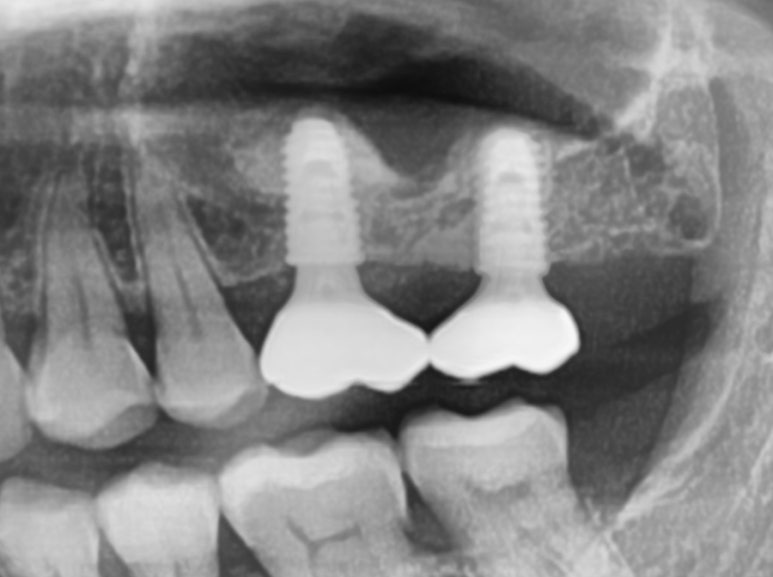

수술 후 4개월 뒤 보철

수술 후 4개월 뒤에 보철물을 올렸고, 1년이상 무리없이 잘 사용하고 계시며, 뼈이식 재료들도 골화되어 엑스레이상 잘 유지되고 있는 모습을 보여주고 있답니다.